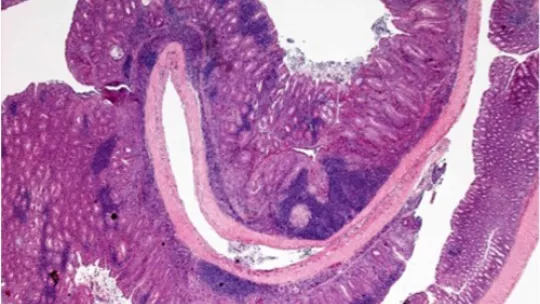

Una de las asociaciones mejor documentadas entre inflamación crónica y tumorogénesis se da en el cáncer colorectal de pacientes que padecen inflamación del intestino.

El cáncer colorectal es el tercero más común en el mundo. Los pacientes con la enfermedad de inflamación de intestino, ya sea por colitis ulcerosas o por colitis de Crohn, tienen un riesgo más elevado de desarrollar este tipo de cáncer.

En un artículo reciente, el equipo de Ángel R. Nebreda describe como p38α es fundamental para el mantenimiento de la buena salud del epitelio intestinal, controla la severidad de las colitis y actúa de supresor de tumores en el colon.

El objetivo principal de este proyecto es investigar como p38α regula la tumorogénesis colorectal asociada a colitis. Los resultados permitirán entender el papel de p38α y sus efectores en la biología del cáncer, así como la interacción entre las células epiteliales y del tejido, a fin de estimar su valor como diana terapéutica o marcador de diagnóstico.